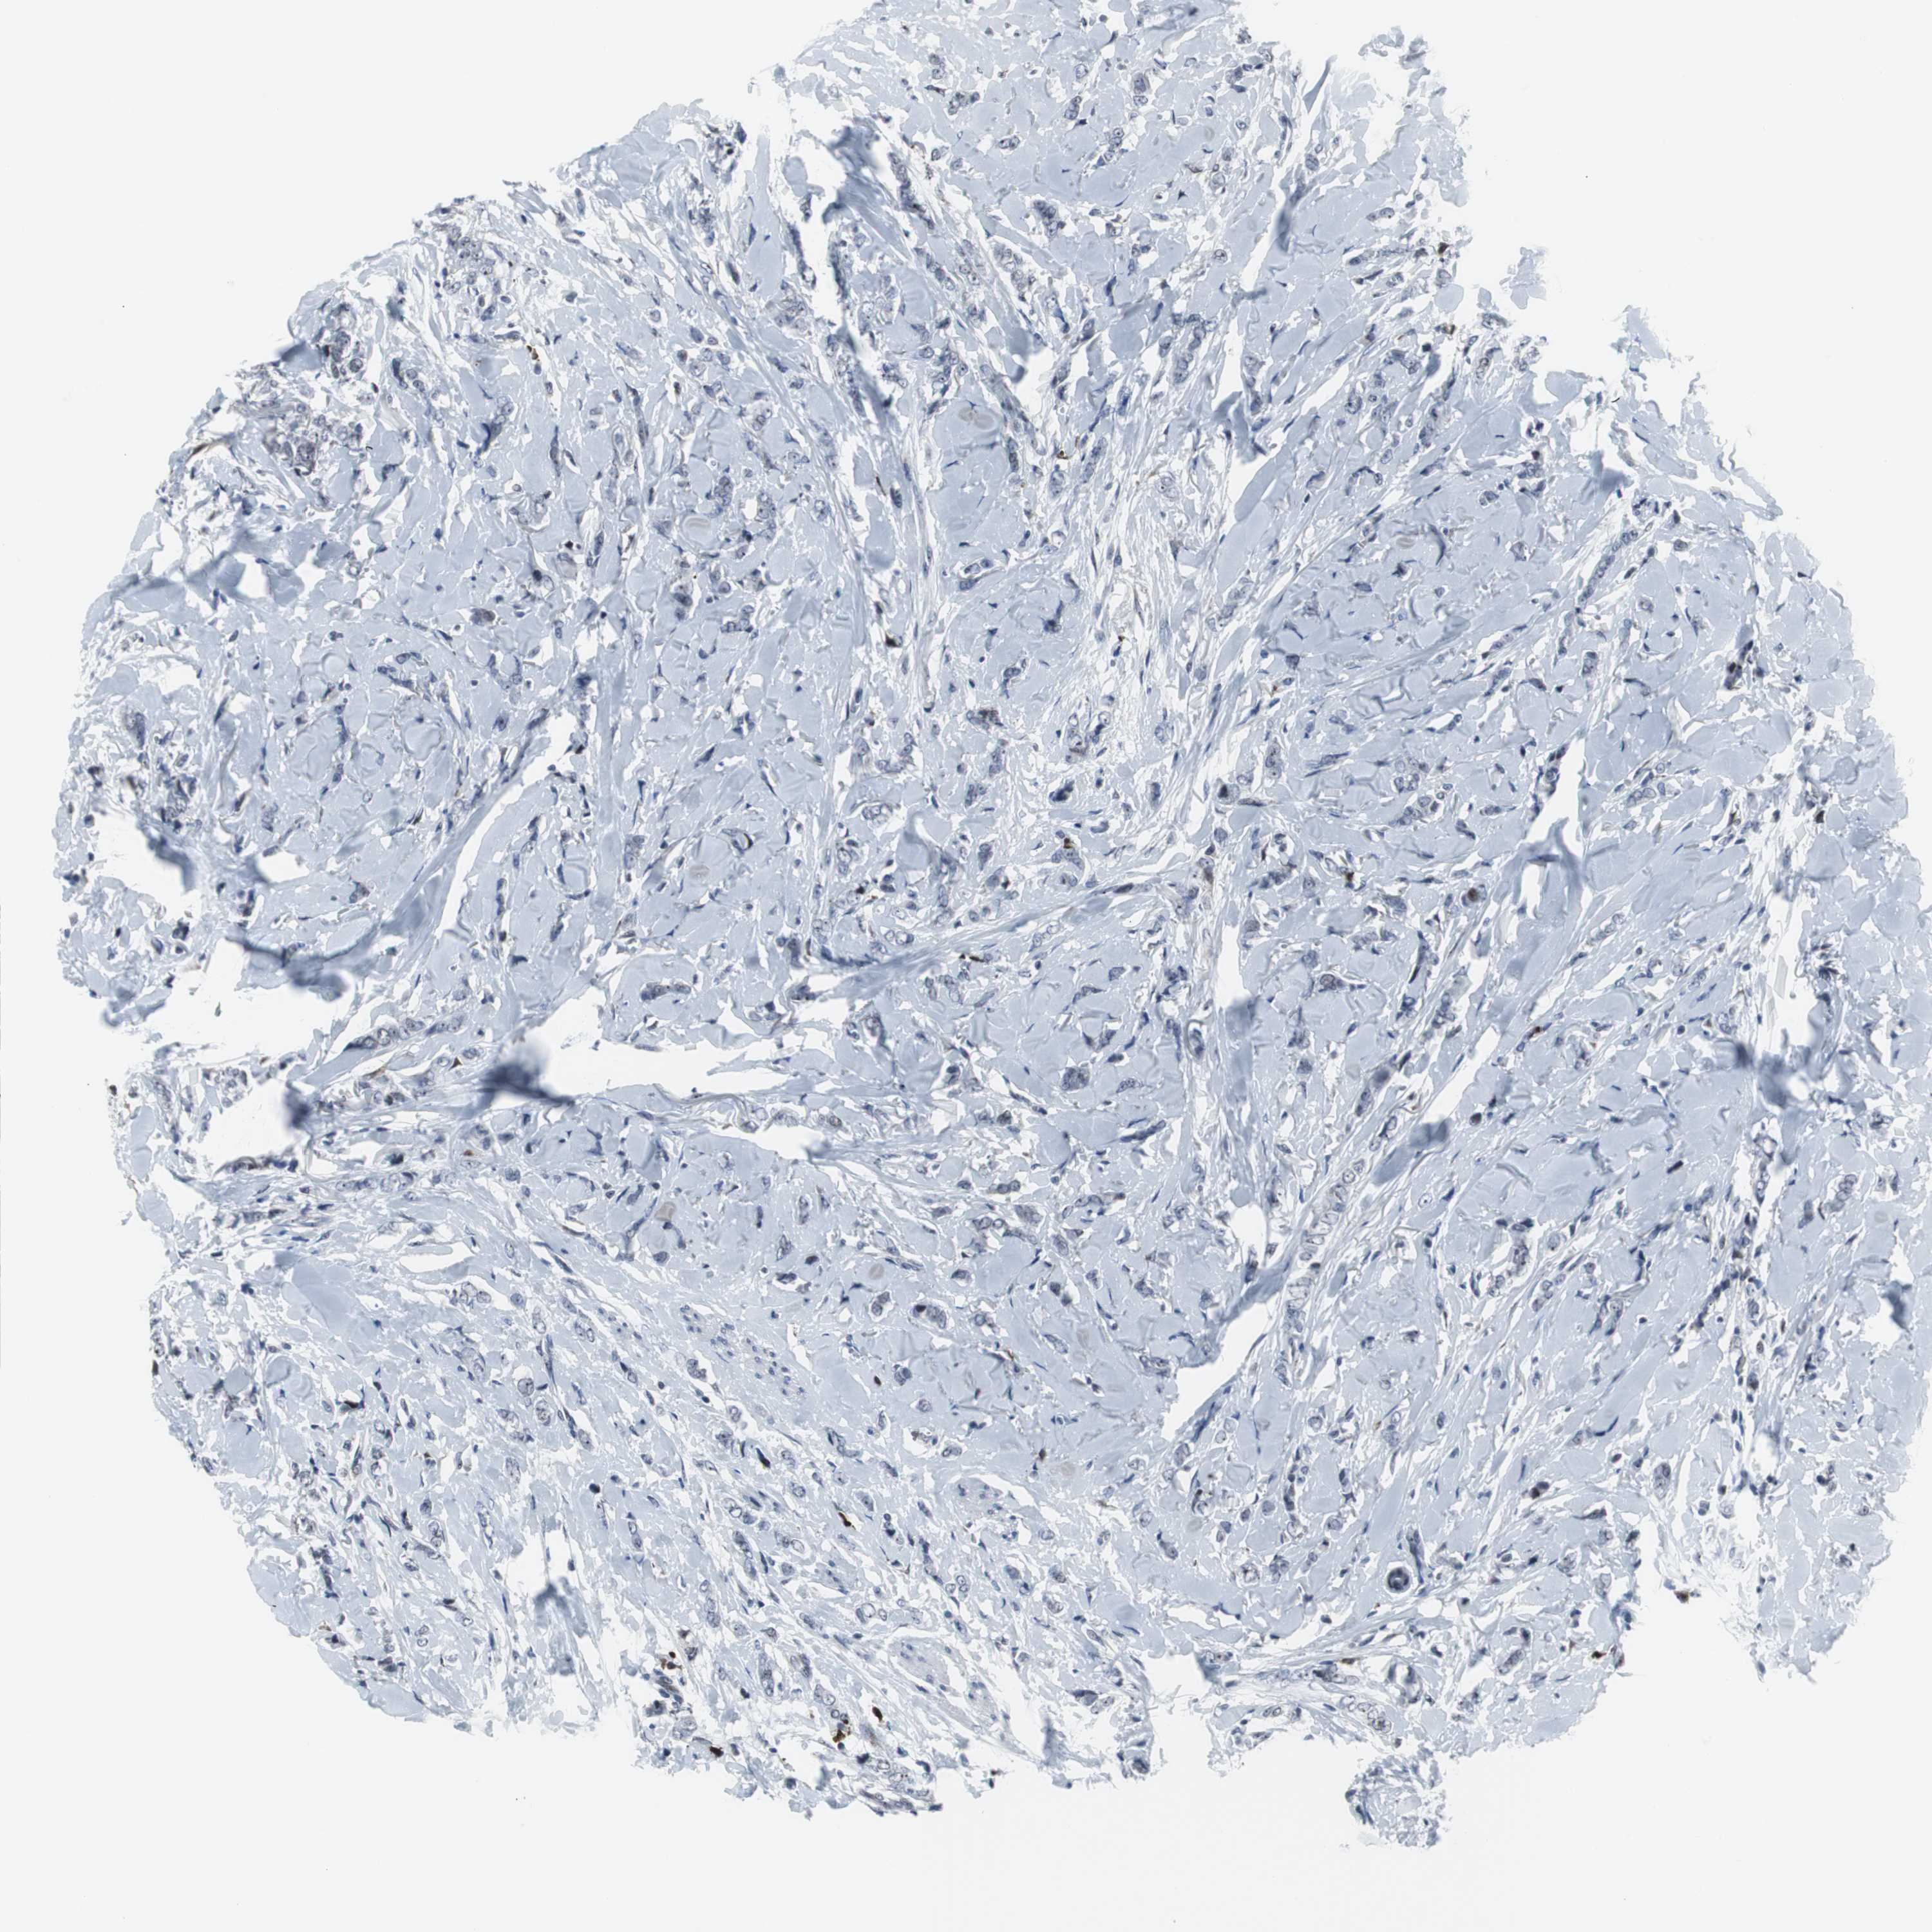

BRCA TCGA BRCA VALIDATION PROTEIN EXPRESSION